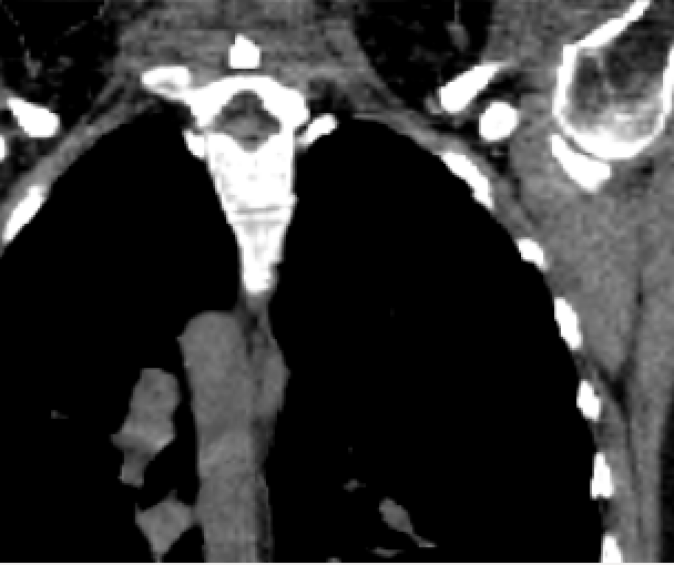

The mean DICE coefficients of the single-atlas registration of the liver and lung masks to the new static patient yield satisfying values of 0.860.12 and 0.960.09. Note the clearly different scan ranges of the data sets (Fig. 2a). The animation of the relevant structures is shown as an example in Fig. 3, using a variable real breathing signal of the target patient (Fig. 2b). In the puncture-relevant liver region, the patient’s breathing states are simulated plausibly for the 4D reference patient (Fig. 3) and, more importantly, the 3D patient (Figs. 4, 5), to which the motion model of was transferred333Demo movie, click here.

We achieve qualitatively plausible results for the liver area in this feasibility study. In the upper thorax especially at the rib cage in neighborhood to the dark lungs stronger artifacts can occur (Fig. 5c). They are due to problems in the inter-patient registration that is a necessary step for the transfer of the motion model. The non-linear deformation sometimes is prone to misaligned ribs. The same is true for the lower thorax with perforation first of the liver and then diaphragm (Fig. 4c). Further optimization have to be carried out as artifacts can appear on the high contrast lung edge (diaphragm, ribs) with a small tidal volume. For liver punctures only, the artifacts of smeared ribs are minor as can be seen in Fig. 4.